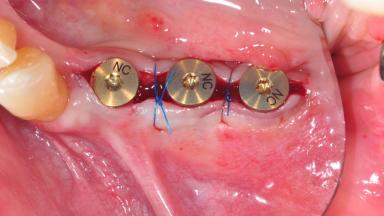

After the placement of three diameter-reduced two-piece implants the bone is augmented with autologous bone chips and DBBM particles to enlarge the crest volume. The surgery is completed with the application of two membrane layers and primary wound closure.

Bone Augmentation Horizontal|Simultaneous

Augmentation Materials Autogenous chips|Xenogenous|Membrane

Bone Volume Deficient horizontally, allowing simultaneous augumentation